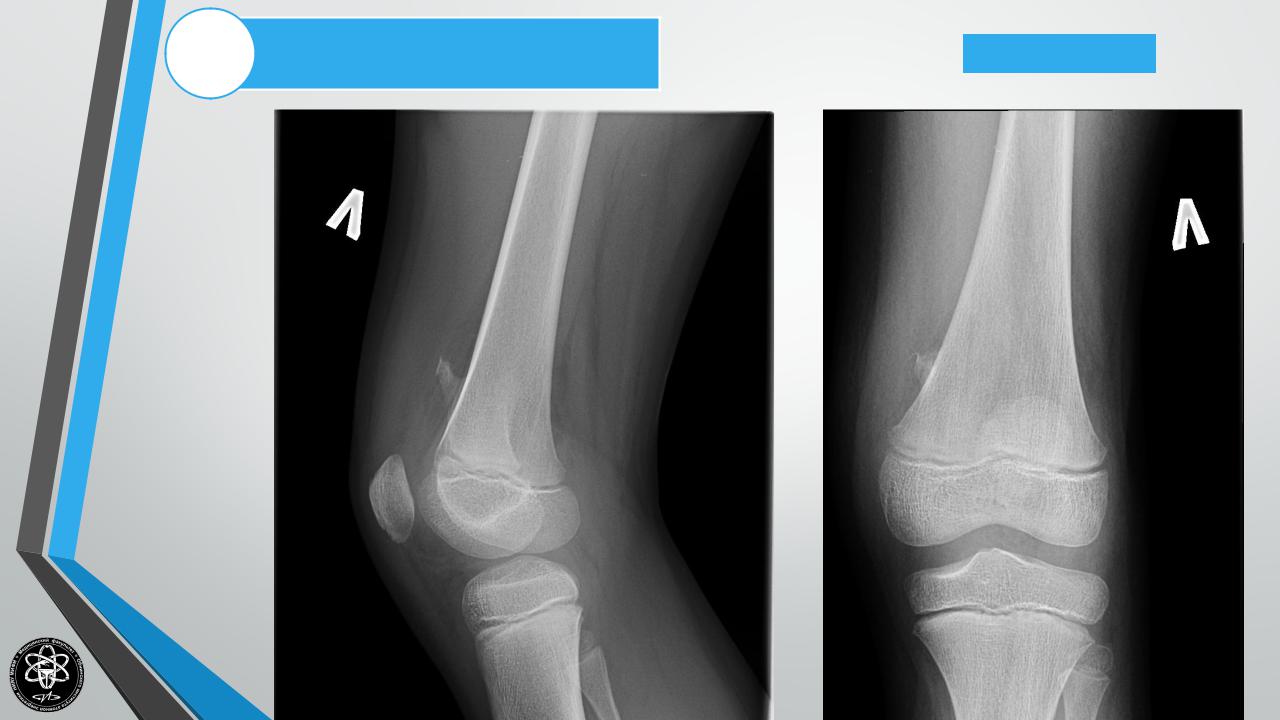

Рентгенологическоеисследование

Остеохондрома